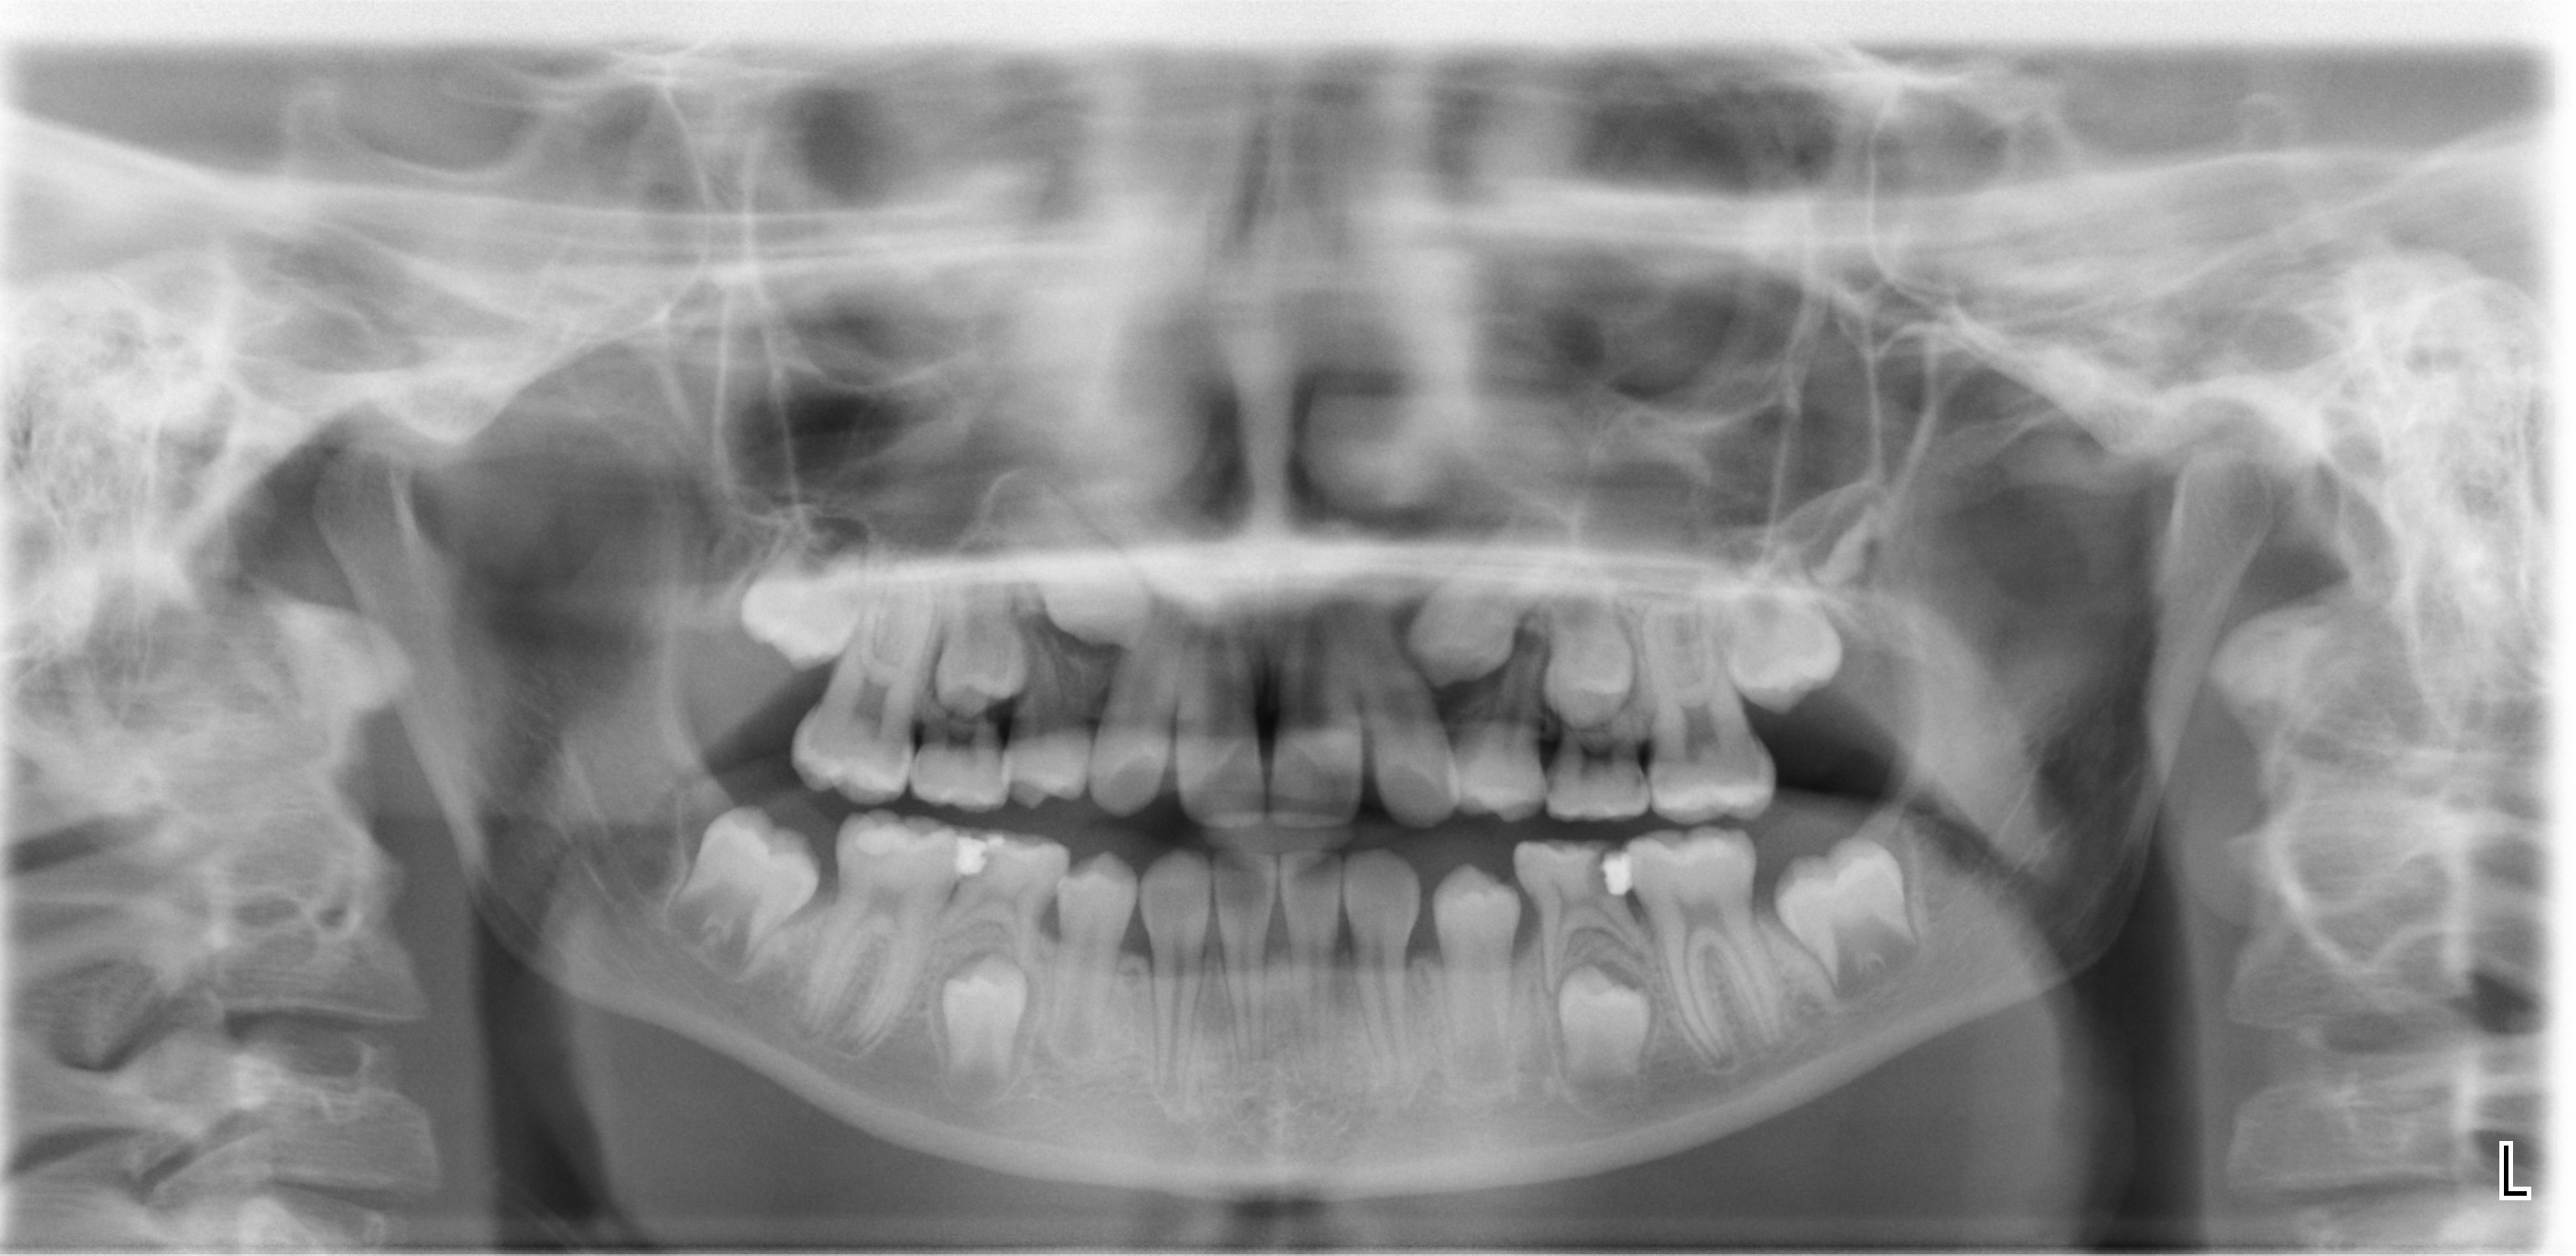

ORTOPANTOMOGRAFIA

Agenesia degli incisivi laterali permanenti inferiori.

Si nota grave affollamento superiore.

RADIOGRAFIA PANORAMICA

Per poter fare una diagnosi completa a volte si richiede la radiografia panoramica del cavo orale.